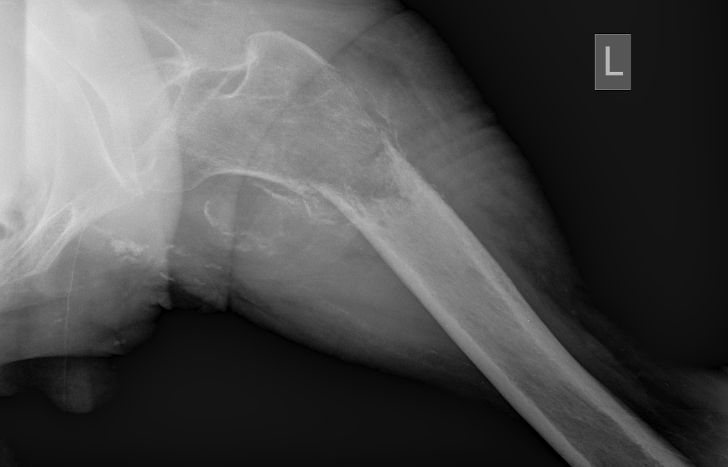

| Subtrochantäre Fraktur | 61-jähriger Patient mit schlecht differenziertem Adenokarzinom der Lunge. Jetzt pathologische Fraktur per-/subtrochantär links. Ausgedehnte Tumorosteolyse. ![]() |

Therapie: Schaftendoprothese.![]() | ||